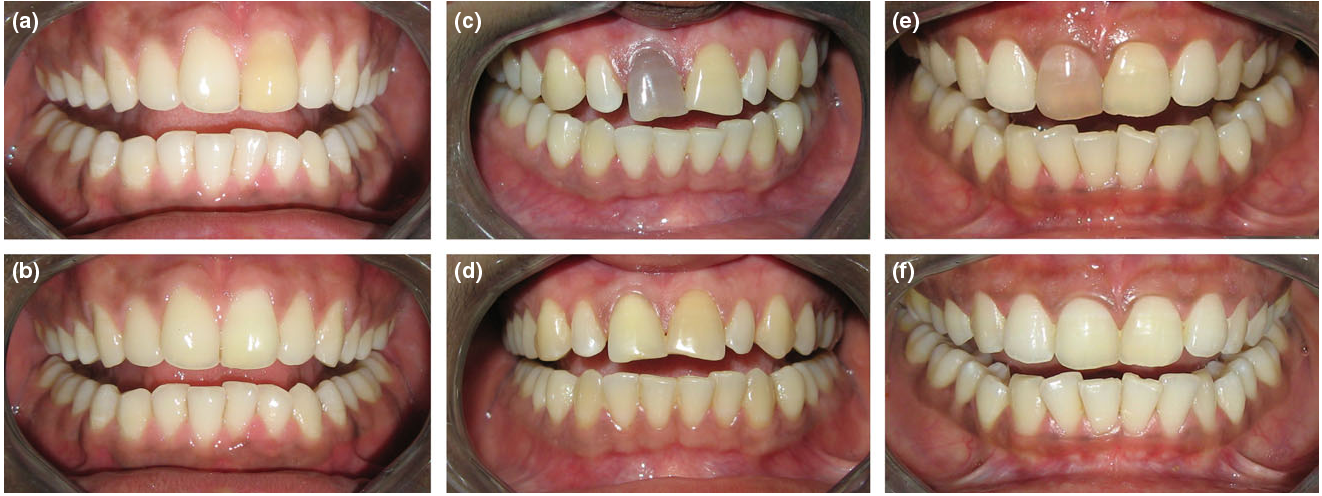

میزان موفقیت و طول عمر بلیچینگ داخلی دندان

بلیچینگ داخلی دندان عصب کشی شده نرخ موفقیت بالایی دارد. میزان موفقیت این روش در حدود 70 تا 90 درصد گزارش شده است. این یعنی در بیشتر موارد، این روش میتواند به طور موثر رنگ دندانهای تغییر رنگ داده را روشنتر کند.

طول عمر نتایج بلیچینگ داخلی دندان نیز نسبتاً خوب است و میتواند بین 1 تا 3 سال یا حتی بیشتر دوام داشته باشد. ماندگاری نتایج به عوامل زیر بستگی دارد: